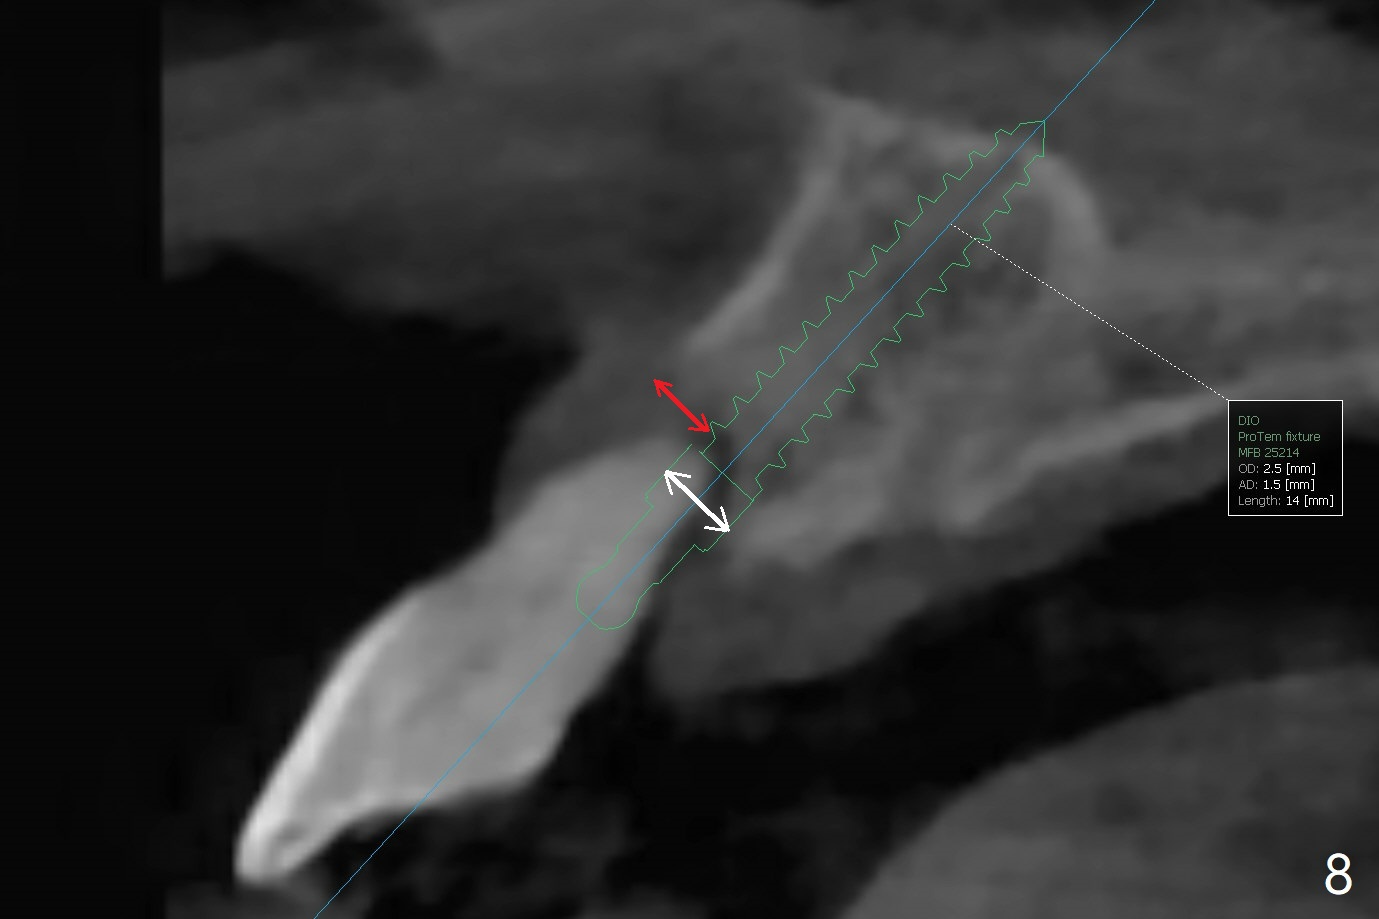

59岁女今天就诊,“上门牙快掉下来”,检查表明右上1延长(图一:长箭头),牙龈退缩(短箭头),红肿(*),颊侧骨板触诊不觉得塌陷(图二)。咬合时,患牙前移(图三),伸长的下切牙(图三,九:1,2)造成咬合创伤。因此拔牙前,将降低下门牙切缘(图四,五(黑色)),为临时牙冠创造足够修复空间。CT冠状切面显示颊侧(图六:B)骨板缺失,可以植入两段式植体(3.5x11.5 毫米),但是最细基台(4毫米直径,图七(粉红色和蓝色))显得太粗,不利于腭侧修复空间形成,而2.5x14(4)毫米一段式植体不仅创造更多颊侧植骨空间(图八(红箭头)),而且由于固有基台直径小(白箭头),容易形成腭侧修复空间。一旦前牙植体永久性修复完成,督促病人做三个第二磨牙植牙修复(图九:7),减少对前牙植牙创伤。临时牙冠不仅解决美观问题,而且固定骨粉,保持颊侧骨板隆起,维持牙龈缘和乳头。在大多数情况下,使用现成树脂牙冠(crown form)制作临时修复物,这个病例牙齿完整,截除的牙冠可以用来做临时牙冠。